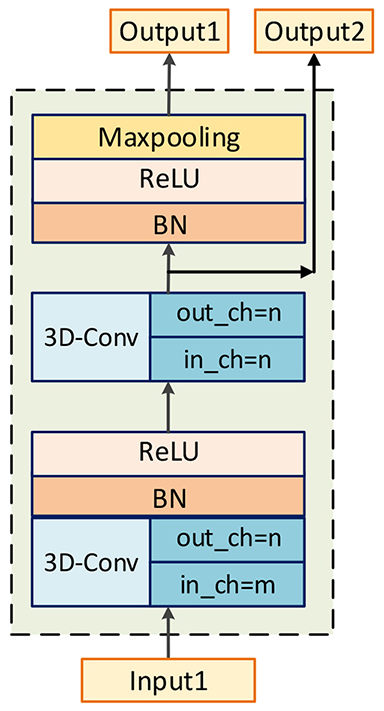

Inspired by U-net [35], our base encoder-decoder network can be seen as a U-net composed with 3D convolutional layers and 3D deconvolutional layers. Through stacking convolutional layers and max-pooling layers, encoder network can get larger receptive field, meanwhile, the spatial resolution becomes smaller. On the contrary, decoder network is composed with 3D deconvolutional layers to upsample feature maps, thus, the spatial resolution of features can recover to original scale when high-level features go through it. As described in [36], higher layers capture high-level representations, which are necessary for recognize targets, and lower layers capture low-level representations such as texture, which play major roles in reducing the missing of tiny structures when we segment objects. Therefore, both content and style representations should be utilized to complete NPC segmentation. Thus, skip connection layers are adopted to combine low-level and high-level features. The architectures of base encoder block and decoder block are illustrated in Figure 3.

Base encoder network. Our encoder network is a VGG-liked [34] network, and the base block is composed with two 3D convolutional layers. According to [37], the representation size should slightly decrease to avoid bottlenecks with enormous compression. Therefore, 3D convolutional layers and max-pooling layers are preferential choices to construct our network. And after convolution, a batch normalization layer and a ReLU layer are followed. There are two outputs produced by encoder block, one is for next encoder block, and the other one is for the corresponding decoder block to realize the combination of high-level and low-level features. There are totally four encoder blocks and the channel number of outputs () is 8, 16, 32 and 64 respectively. It is worth mentioning that there is one single convolutional layer after final encoder block to refine features downsampled by encoder block, and the number of its channels is 64.

Base decoder network. The purpose of decoder network is to map high-level features to target modality. A 3D deconvolotional layer is utilized to upsample feature maps, then, a concatenation layer combines these features with low-level features from encoders with the assistance of skip connection layers. After merging, a convolutional layer is adopted to fuse these feature maps. The numbers of output’s channels for decoder blocks are 64, 32, 16 and 8 respectively.

Finally, the final decoder block is followed by a convolutional layer with sigmoid as activation function to produce final segmentation results.